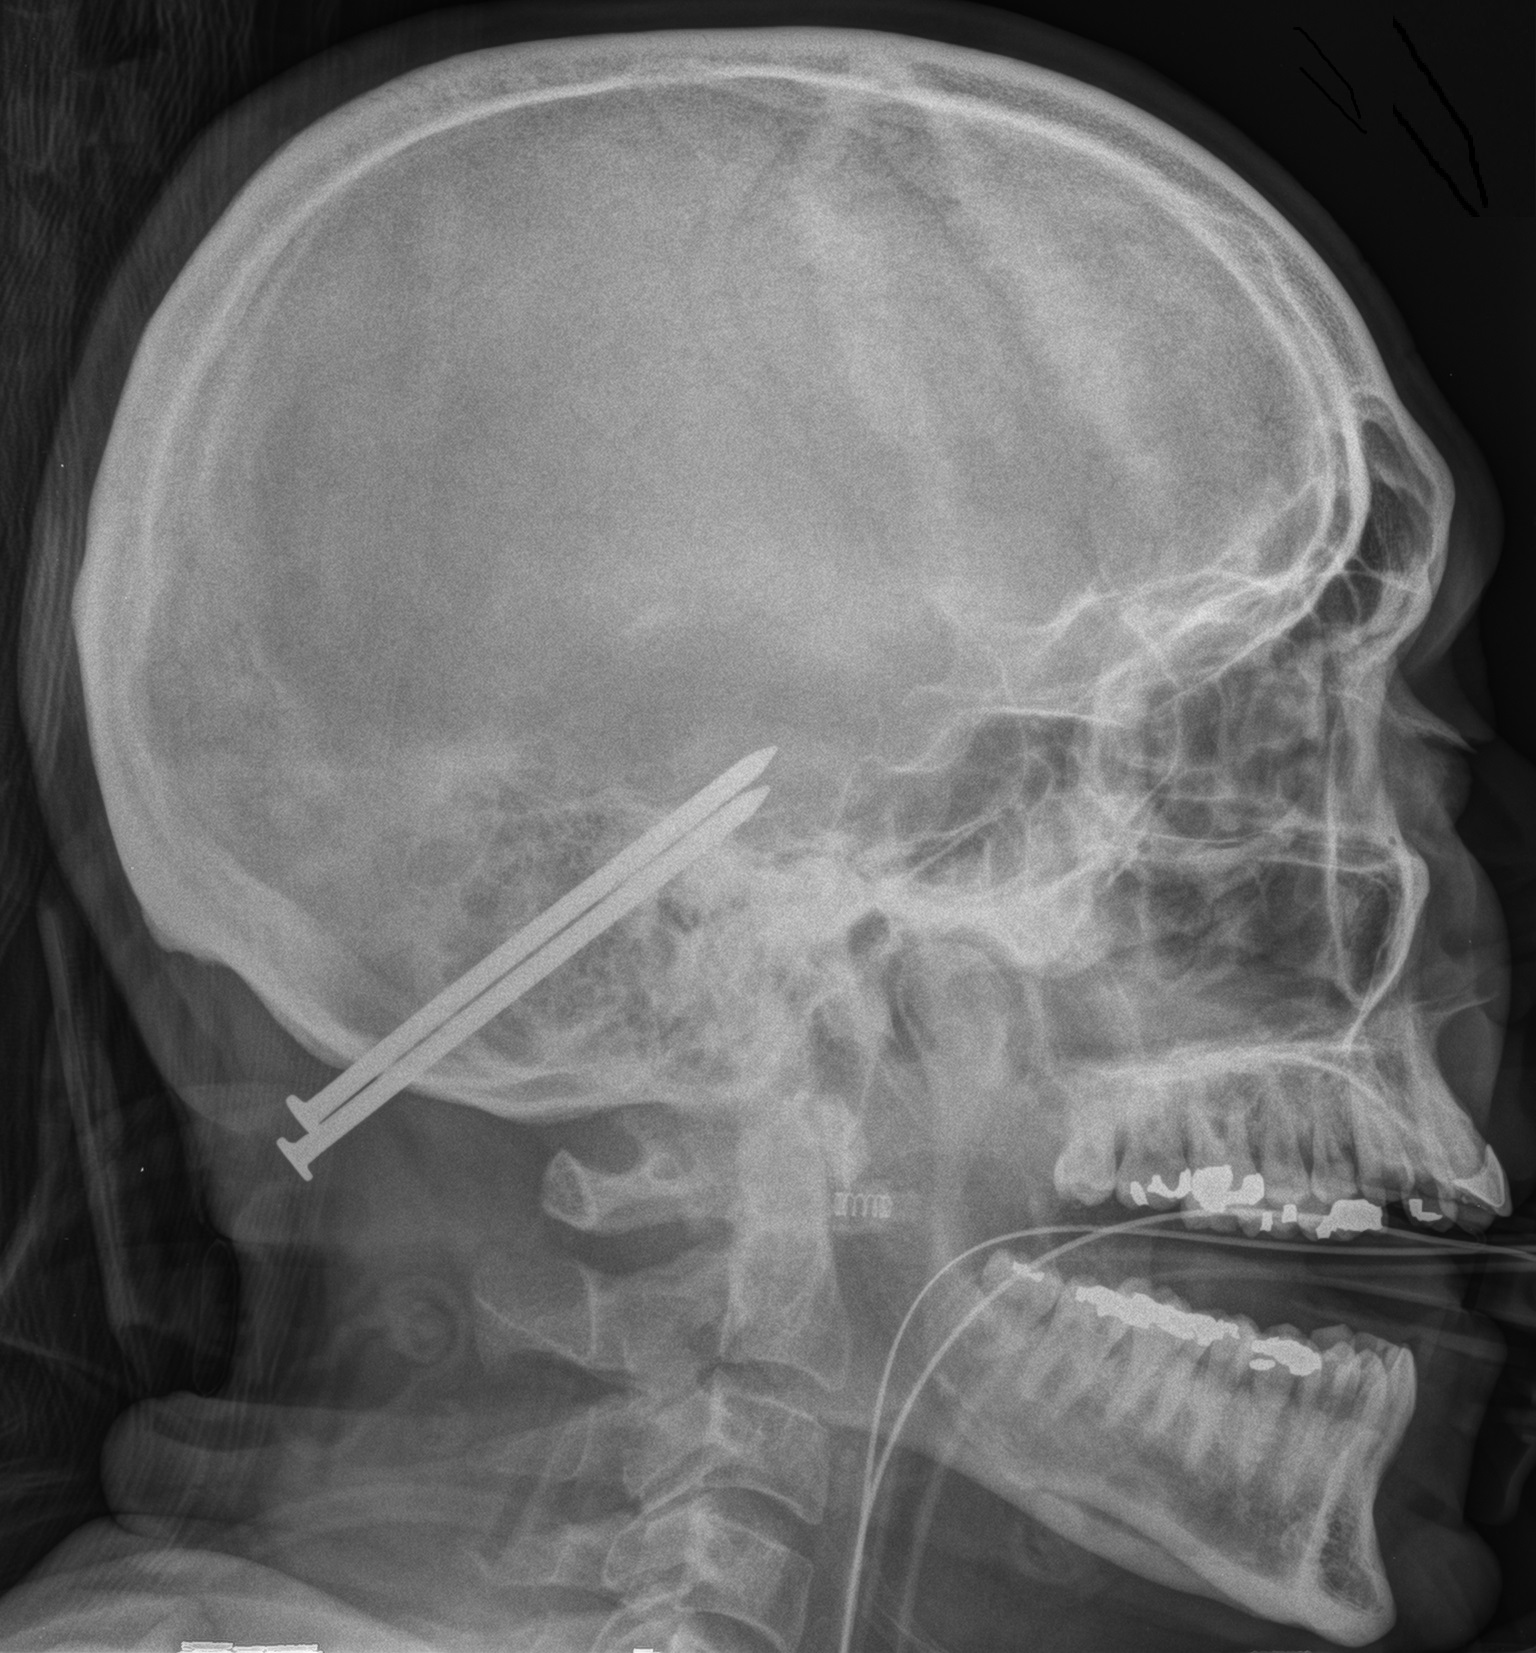

Outcome Prediction in Penetrating Brain Injury

In collaboration with several other trauma

centers (University of Maryland Shock Trauma, Yale, Baylor College of Medicine and Vanderbilt Medical Center), our group has created the SPIN-score (Muehlschlegel S, Ayturk D, Ahlawat A, et al.) to predict survival after penetrating brain injury. We are currently working hard to validate this parsimonious logistic regression prediction score. (This has been featured in Neurology Today).